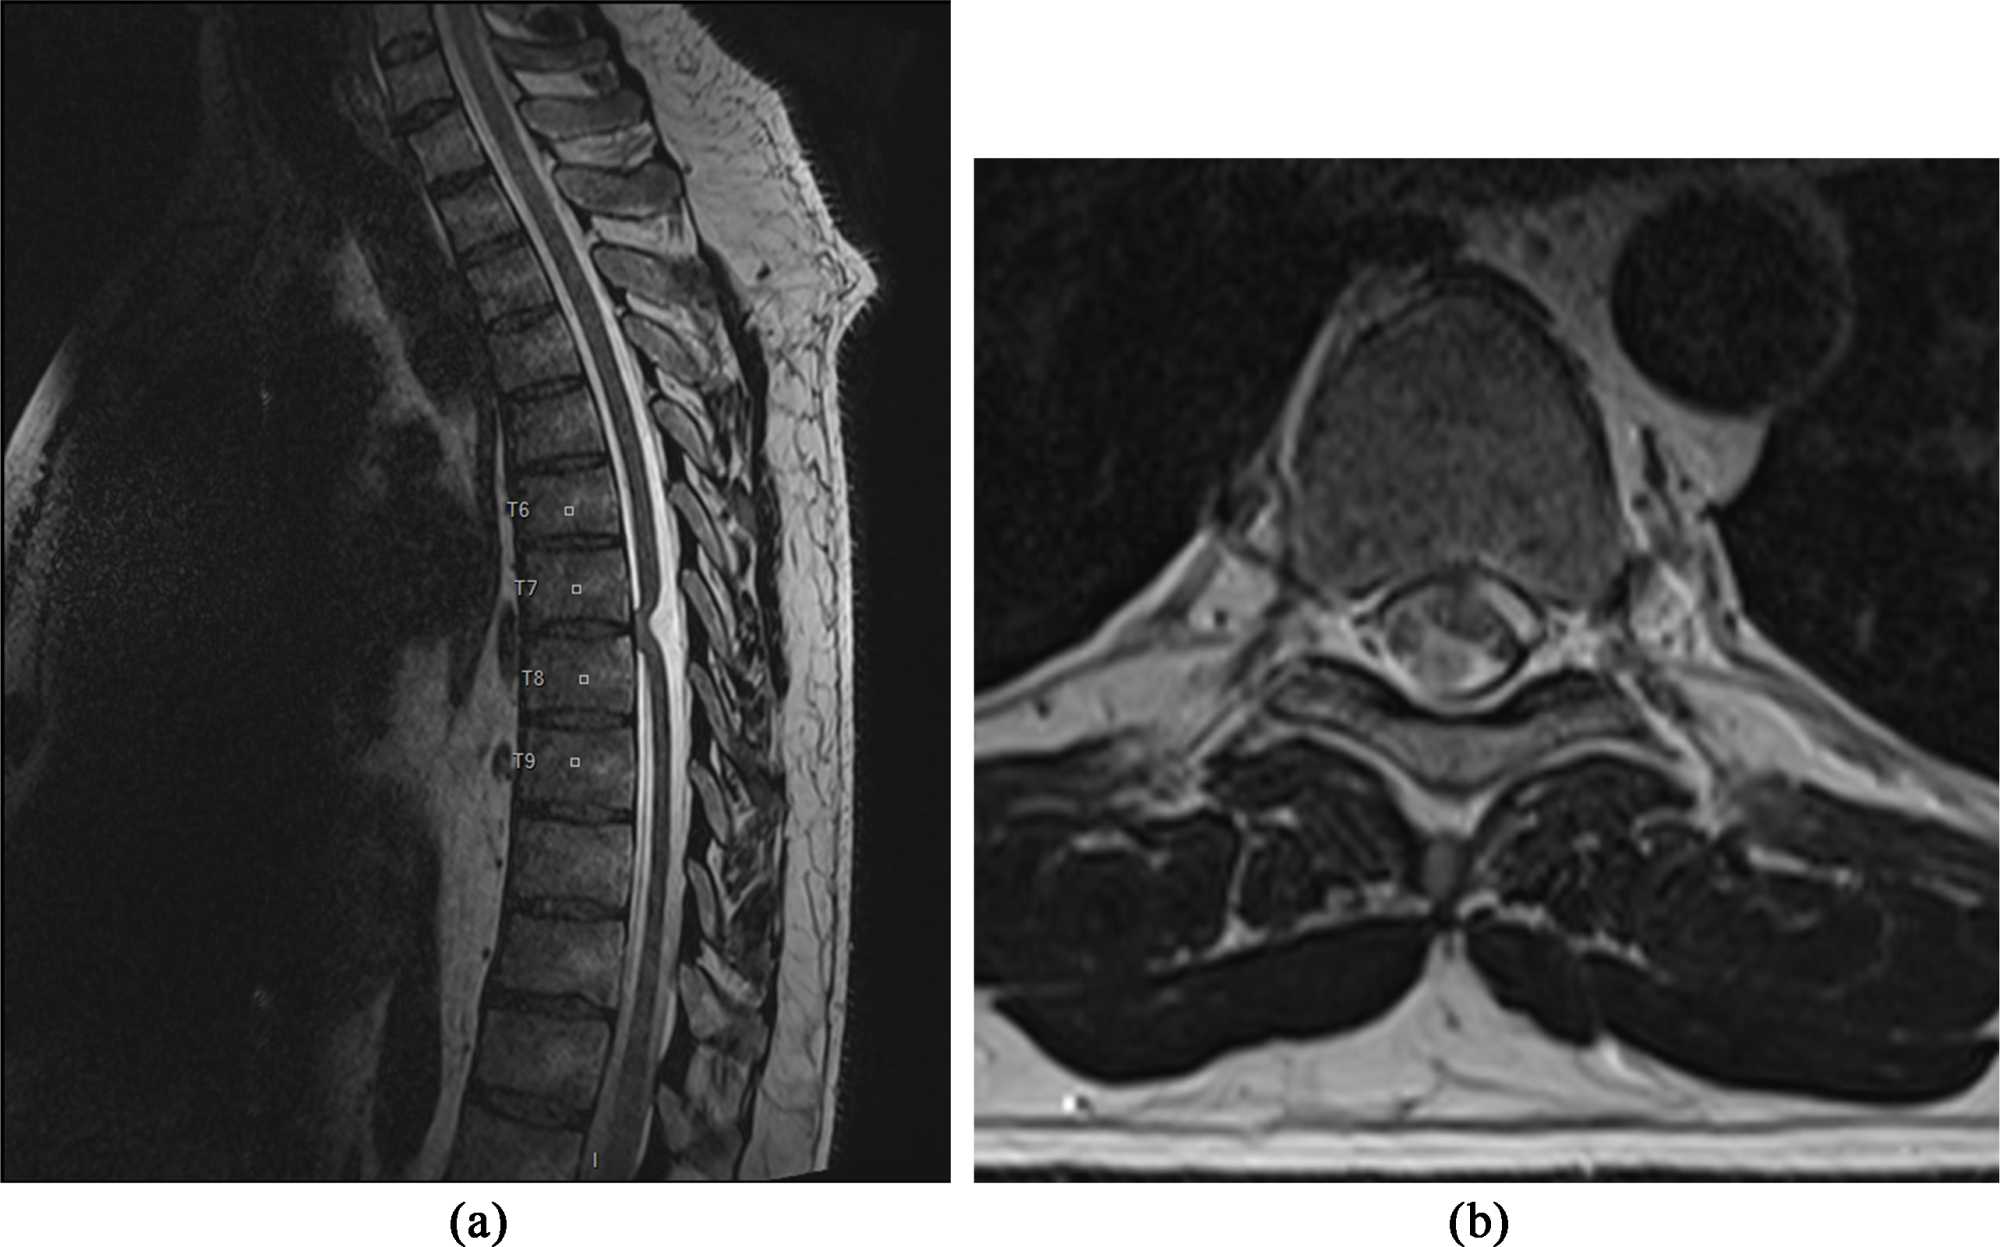

Spinal cord MRI revealed angulation of the medulla at T7-T8, widening of the posterior subarachnoid spaces opposite and discrete hypersignal of the herniated portion of the medulla. This is shown in Figure 1. The diagnosis of SCH was therefore made. Given that the hernia was symptomatic, we decided on surgical treatment. Surgery consisted of laminectomy of T6, T7 and T8, followed by dural opening under an operating microscope. We then located the invaginated portion of the medulla and gently reintroduced it into the dural sheath. Finally, we repaired the anterior dural defect with a synthetic dural patch (Neuro-Patch®). Clinically, the postoperative course was marked by an improvement in symptomatology, with recovery of motor strength in the left lower limb and an improvement in sphincter disorders. However, sensory disturbances persisted 18 months after surgery. Post-operative MRI showed no SCH in Figure 2.

Figure 1. Preoperative thoracic spinal cord MRI T2-weighted sequence. (This imaging was performed after the patient’s physical examination, and was used to establish the diagnosis and surgical indication.) (a) Sagittal section showing anterior deviation of the medulla with angulation; (b) Axial section showing the marrow abutting the dura mater.

Diagnosis is made by MRI. Sagittal slices show an anterior deviation of the medulla with discrete angulation, while axial slices show invagination of the medullary cord into the epidural space. The differential diagnosis is a posterior arachnoid cyst [9]. However, this arachnoid cyst may be associated with 20% to 25% of SCH cases [11].